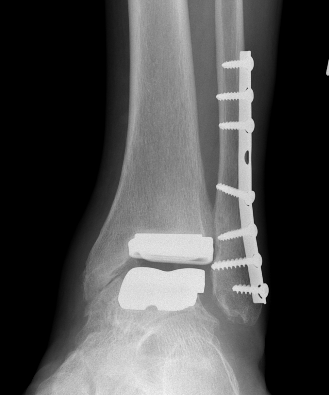

Loosening

Options

Athrodesis

Revision TAR

Arthrodesis

Revision

Gross et al Foot Ankle Spec 2015

- systematic review of arthrodesis for failed TAR

- 80% union rate